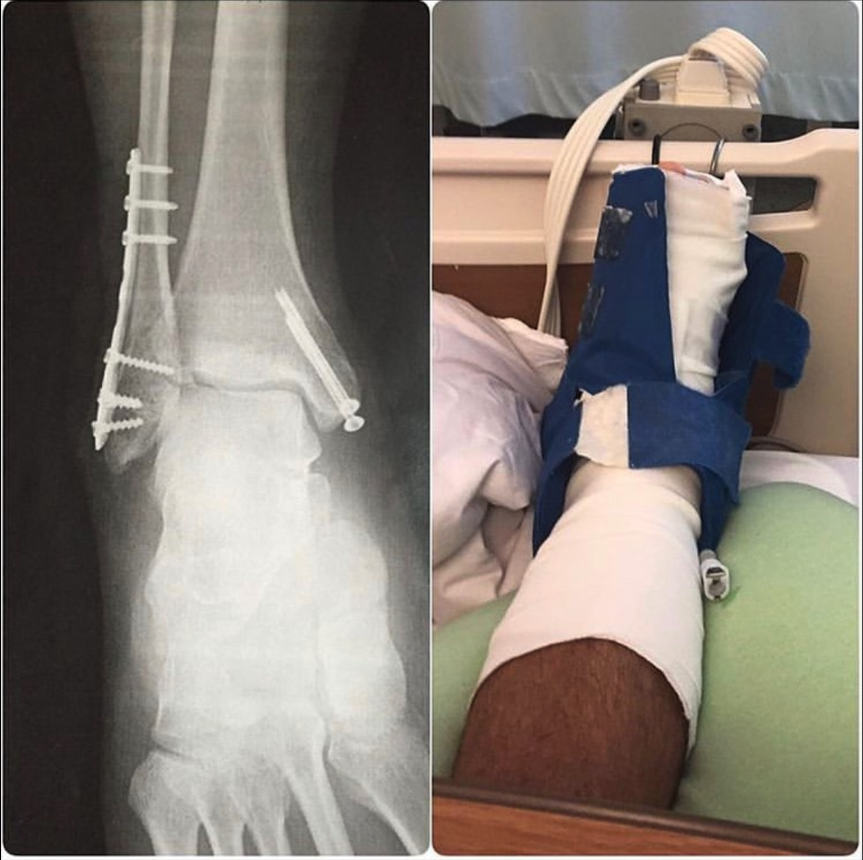

• Surgery for ankle break at 40-ish from a fall in skateboarding… yeah, I know, I know.

I was a blue belt in Brazilian Jiujitsu when I broke my ankle. I was gung-ho about BJJ, and there was no way I was going to take three months off from training. I was smart about it, and not only did I fully recover, but I also improved my BJJ during that time. Here’s how I did it using those two questions above.

• What do I need to do to heal myself?

After my reconstructive surgery, I followed my doctor and physical therapist’s advice to the T.

I didn’t try to add extra training or rehab moves into the mix. In other words, I didn’t try to drill, spar, run, or anything else until my doctor and physical therapist told me I was cleared to do so.

Once I got the OK, I EASED into my regular training while working to further improve my strength, range of motion, and ankle control.

In other words, I didn’t do stupid shit that could have re-injured my ankle and messed it up for life.